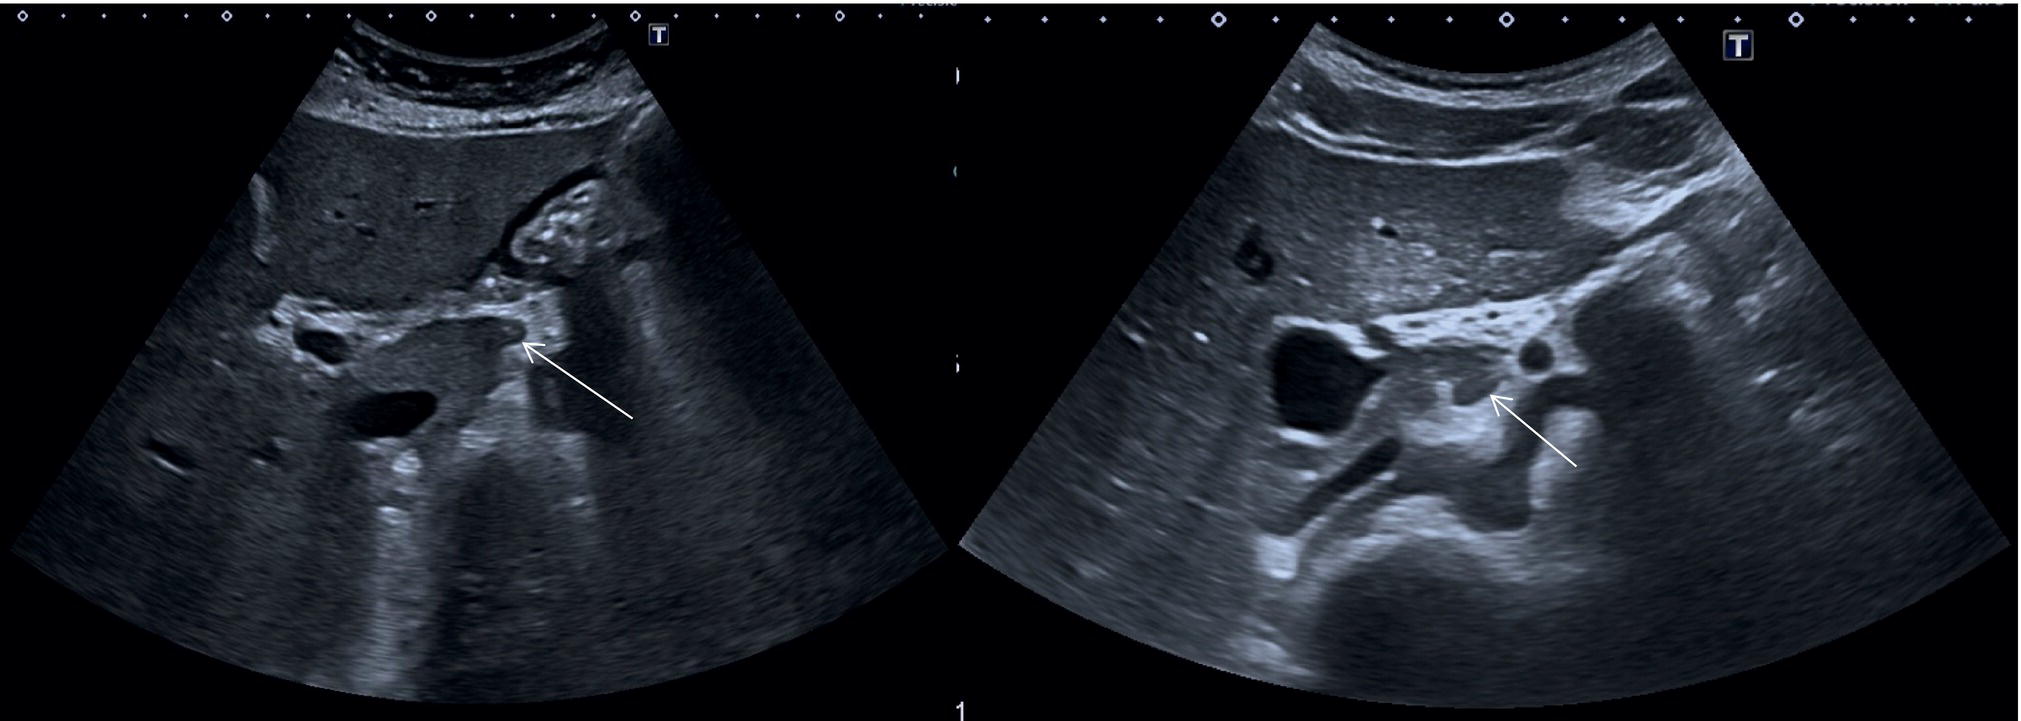

Other anatomical variants include the position of the PV, HA, and CBD at the level of the hepatic hilum. In the majority of cases the PV lies posteriorly, and the HA lies between the PV and the above CBD, while less frequently the HA will run above the CBD (Figure 3.20) or below the PV. The main trunk of the PV usually bifurcates at the porta hepatis into a main left and right branch and a further anterior and posterior branch of the right trunk. Alternatively the PV might have a trifurcation that might be extrahepatic or intrahepatic. The hepatic veins can also show some anatomical variants. With regard to the RHV, this is usually single and dominant, while in a minority of cases there might be an early bifurcation or trifurcation or multiple small RHVs entering the IVC. The most common variant is an accessory right inferior hepatic vein. Both the MHV and LHV can be double and sometimes form a common trunk that drains independently into the IVC. When the hepatic veins are duplicated, typically the larger is used for segment classification. The caudate lobe might have a single vein or several small hepatic veins that drain independently and directly into the IVC. The HA can have several anatomical variants, especially with regard to its origin. The most common is directly from the aorta or the superior mesenteric artery. All these vascular variants do not have pathological implications, but should be kept in mind since they have important technical implications in a case of liver transplant, resection, or embolic treatment of liver tumours [7]. Rare vascular anatomical variants include congenital portal venous shunting (see Chapter 11).

Other anatomical variants include the position of the PV, HA, and CBD at the level of the hepatic hilum. In the majority of cases the PV lies posteriorly, and the HA lies between the PV and the above CBD, while less frequently the HA will run above the CBD (Figure 3.20